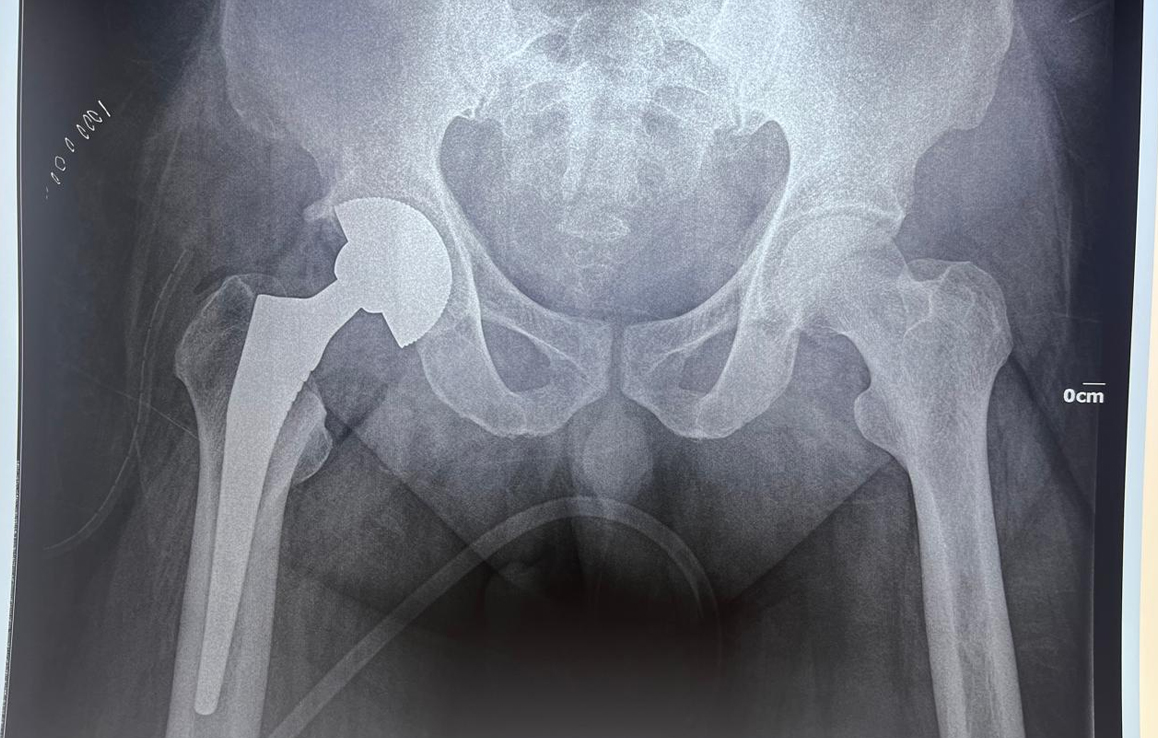

A 32-year-old male with a 7-year history of hip osteoarthritis underwent total hip replacement in 2018, with reconstruction of a false acetabulum using bone graft and screws. A recent X-ray shows a well-fixed implant in good alignment, and the patient reports pain-free walking with a good range of motion.